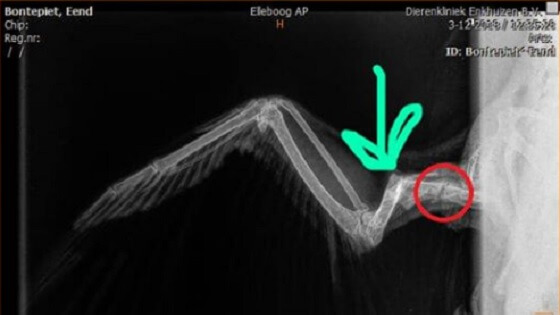

Op voetbalclub gewond geraakte eend kan nooit meer vliegen

Die eend die afgelopen weekend in het nieuws kwam omdat er met het dier gevoetbald zou zijn, zal nooit meer kunnen vliegen. De vogel heeft twee breuken in haar vleugel, een oude breuk en een nieuwe. Kinderen van voetbalclub Always Forward in Hoorn, of van…